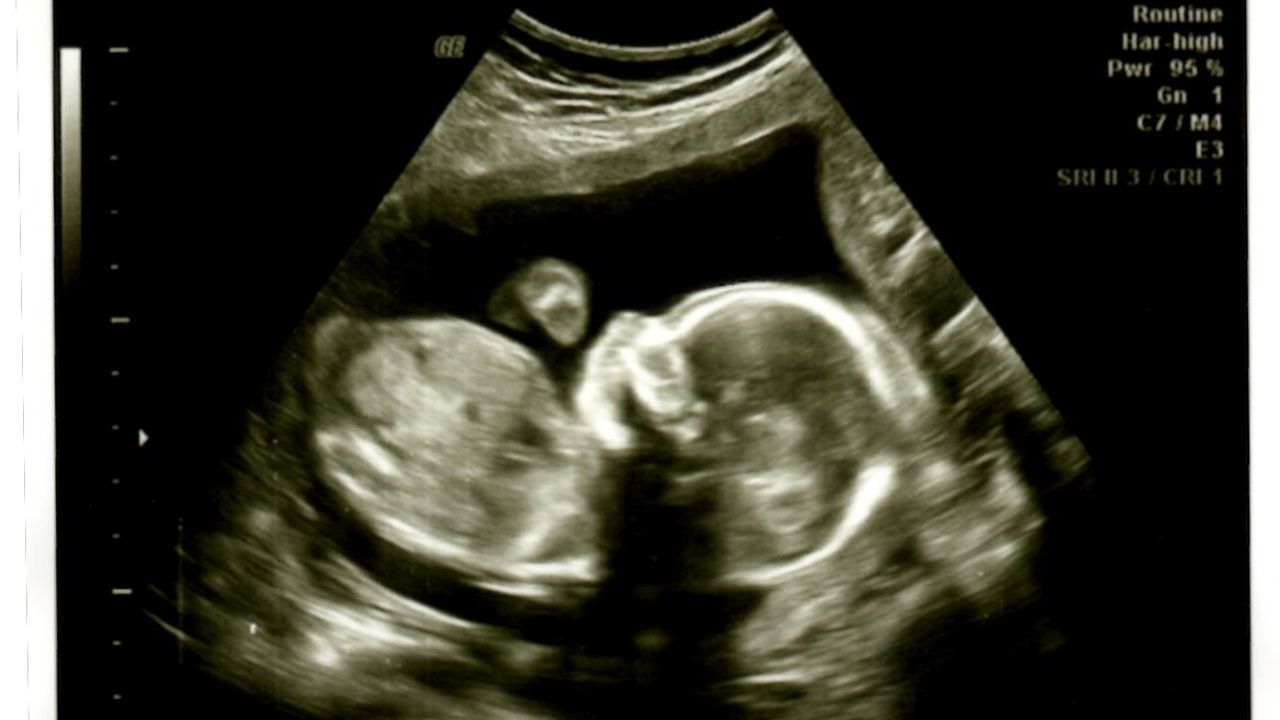

İşte ultrason kağıdında bebeğin boyuna dair ipuçları:

Gebeliğin 14. haftasından sonra bebek kıvrık durduğu için baştan ayağa tam boyunu ölçmek zorlaşır. Bu nedenle, bebeğin genel büyümesi ve boyu hakkında fikir veren farklı kemik ölçümleri kullanılır:

- FL (Femur Length - Uyluk Kemiği Uzunluğu): Bu, bebeğin uyluk kemiğinin (vücuttaki en uzun kemik) uzunluğunu gösteren ölçümdür. Genellikle milimetre cinsinden ifade edilir. FL, bebeğin iskelet gelişimini ve dolaylı olarak boy uzunluğunu değerlendirmede çok önemli bir parametredir. Bazı formüllerle (örneğin FL x 7 gibi) bebeğin yaklaşık boyu tahmin edilebilir, ancak bu sadece bir tahmindir.